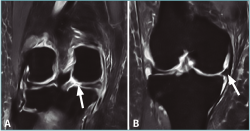

Se considera lesión de la raíz a la avulsión de la misma del hueso con o sin fragmento óseo (Figura 1), o bien a la rotura (normalmente radial) de la región adyacente al mismo (< 1 cm) (Figura 2)(3). Esta puede ser de naturaleza degenerativa o traumática (generalmente asociada a lesiones ligamentosas de la rodilla).

Figura 1. Avulsión de la raíz posterior del menisco lateral (ML) con fragmento óseo (flecha: fragmento óseo avulsionado).